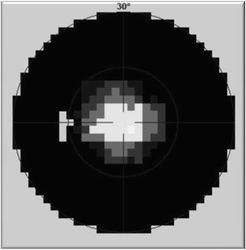

Vyšetření statickým počítačovým perimetrem - zorné pole před

Vyšetření statickým počítačovým perimetrem - zorné pole po

U druhé pacientky B.J., nar. 1974 trvala konstrikce zorného pole

na 10 až 20 st. 5 let, v průběhu kterých prodělala opakovaně náročná

vyšetření, marně hledající příčinu zúžení. K rozšíření zorného pole

došlo spontánně v 18 letech věku nemocné. Rozšíření si dáváme do

souvislosti s nabytím určité svobody a volnosti, ve které byla dříve

přísně omezována.